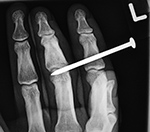

| Nail gun injury |

Left index finger middle phalanx nail gun injury |